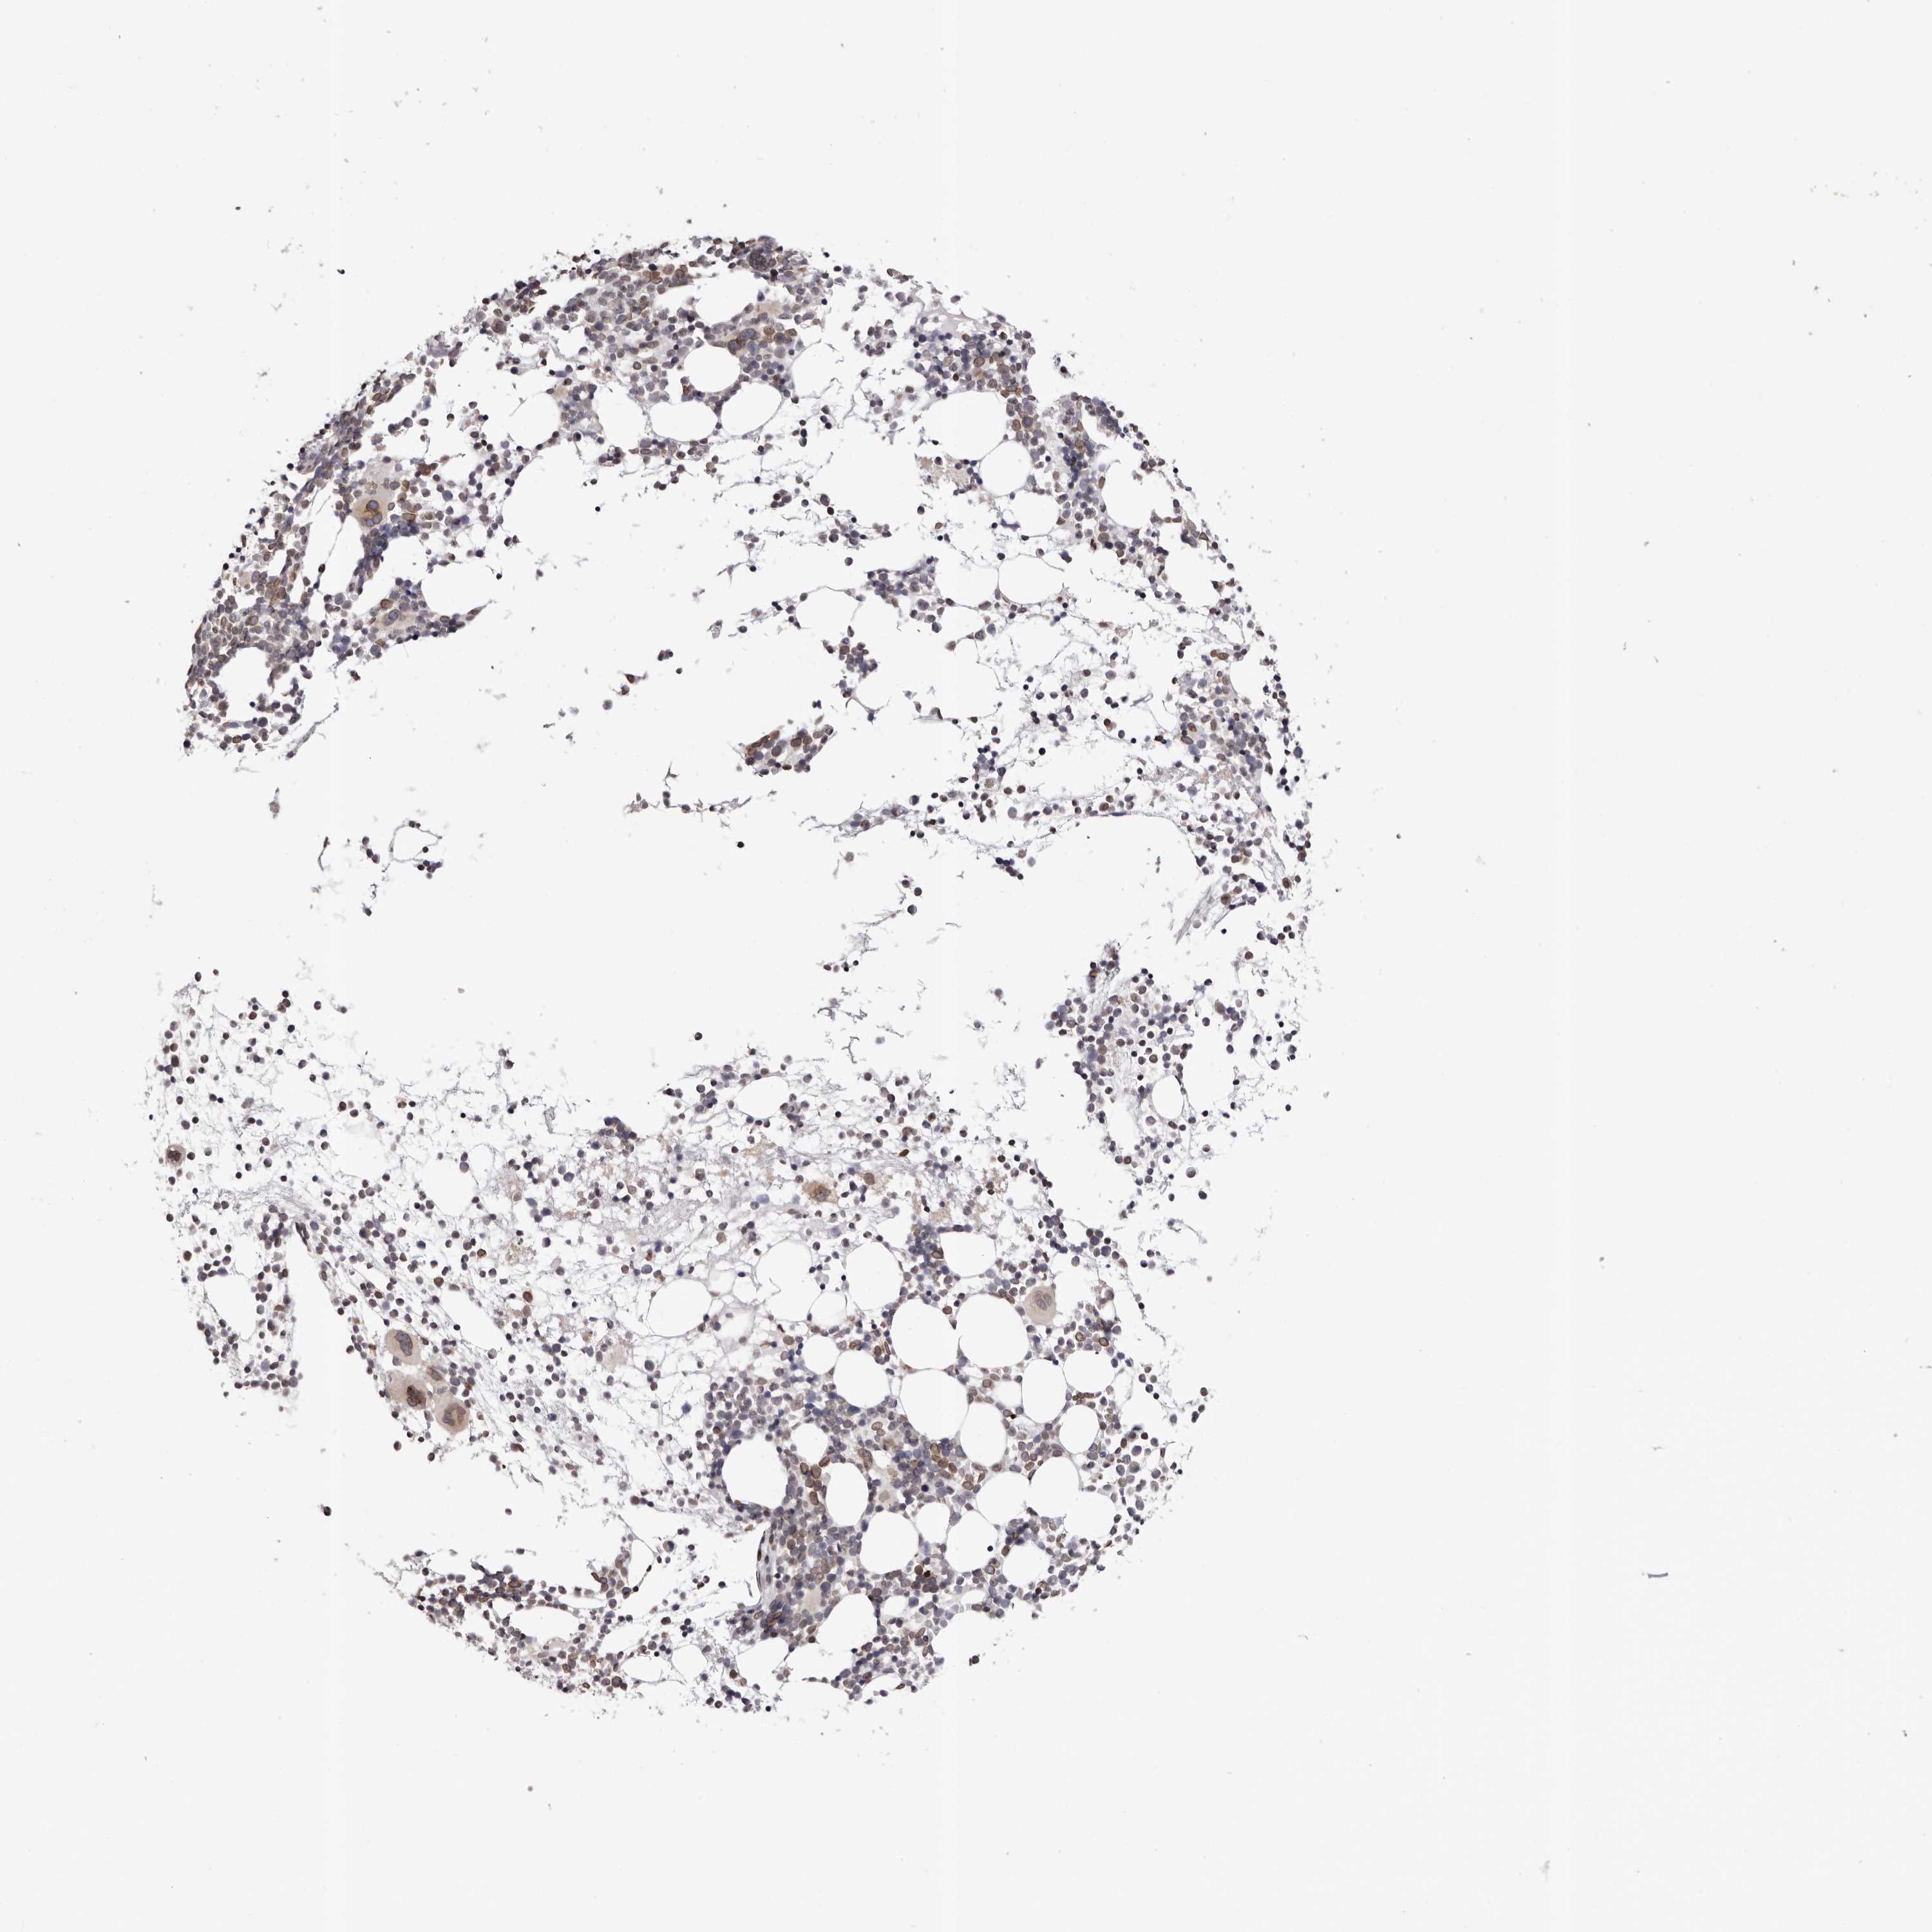

BONE MARROW - Antibody stainingi

Antibody staining in the annotated cell types in the current human tissue is reported as not detected, low, medium, or high, based on conventional immunohistochemistry profiling in selected tissues. This score is based on the combination of the staining intensity and fraction of stained cells.

Each image is clickable and will lead to virtual microscopy that enables deeper exploration of all samples and also displays staining intensity scores, fraction scores and subcellular localization as well as patient and tissue information for each sample.

Antibody HPA027896Antibody HPA027897Antibody HPA027898

Hematopoietic cells MediumMediumMedium